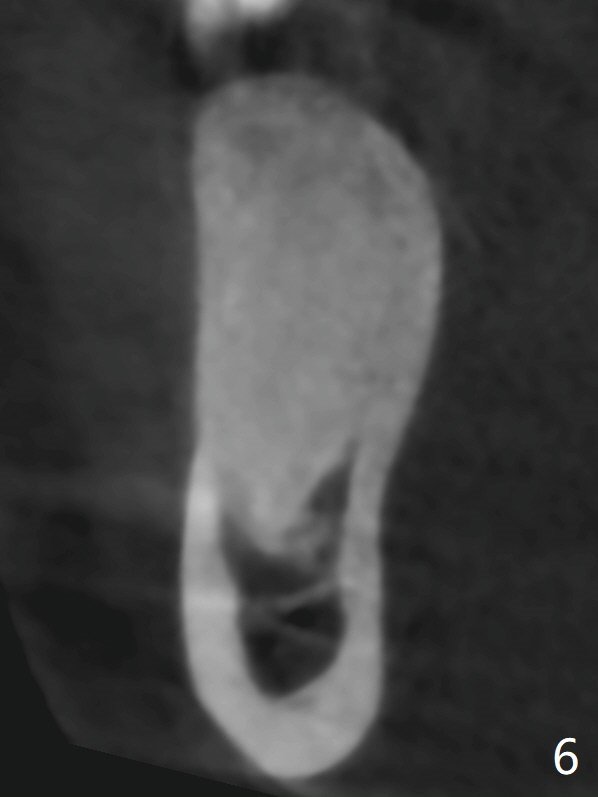

CT is taken 4 months post panoramic X-ray (Fig.2).  C: coronal; S: sagittal; A: axial; B: buccal.  Coronal (Fig.6) and sagittal (Fig.7) sections.  It seems that the lesion does not invade the thin buccal plate or the periodontium.